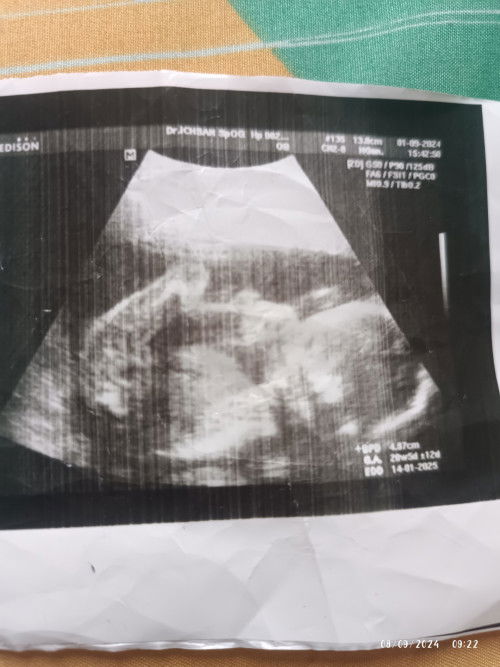

Kata dokter alhamdulillah sehatt,janinnya d dalam rahim,posisi bagus,detak jantungnya bagus juga#Sharing_dong_Bund 🤲,,stelah di vonis s bidan abal abal tu aku hamil d luar rahim😡

Bun pertama aku cek kehamilan aku tespack hasilnya positif dan aku langsung ke bidan untuk usg kehamilanku ini ,kata si bidan "iya ini hamil,hamilnya 6w3d"gitu katanya,langsung d vonisnya aku terkena hamil d luar rahim,ini tidka bisa d selmatkan,wlaupun dia berkembang nnti janinnya bisa pecah dan bisa menyebabkan pendarahan yg hebat,d situ aku sudah down mental ku bun😭dan hbis usg d kasihlah aku vitamin,suruh dtg 2 minggu lagi katanya,,,tapi d posisi ini aku bnar² sudah down bun,,aku berjanji nggak bakalan mw balik ke sini lagi,,dgn keyakinan aku aku dtglah k dokter d hari yg sma dan langsung masuk k ruangan usg dokte,,d sini aku terkejut apa kata si dokter ini🫣"alhamdulillah selamat ya bu,ibu hamil 4w6d,d sini dokter blg ini masih kantongnya y bu,trus oikiran aku masih terngiang² kata s bidan itu lalu ku tanyain lah,dok kantong janin nya d dalam apa d luar rahim? Lalu dokter jwb,,alhamdulillah ini didalam rahim kok bu,,bagus letak kantong dan posisinya,mmng dokter blg ini kandungannya lemah,tapi si dokter langsung kasih aku obat penguat dan vitamin asam folat,, Bagaimana pendapat moms,,ada yg pernah sama nggak sma aku lngsung d vonis yg nggak²🥺🥺#SeriusTanya #Sharing_dong_Bund #bantujawab #ingintahu #bantusharing